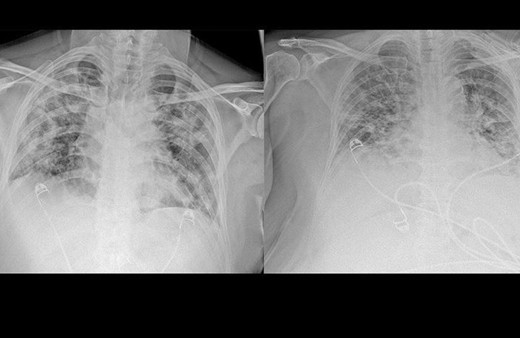

Akciğer